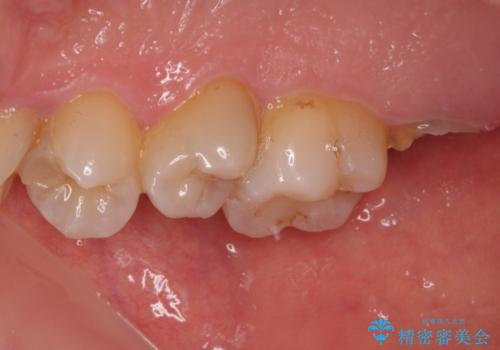

抜歯後に不快感は消失したのですが、手前の歯にあるむし歯が痛み出してきたため、セラミックインレーにて修復治療を並行して行いました。